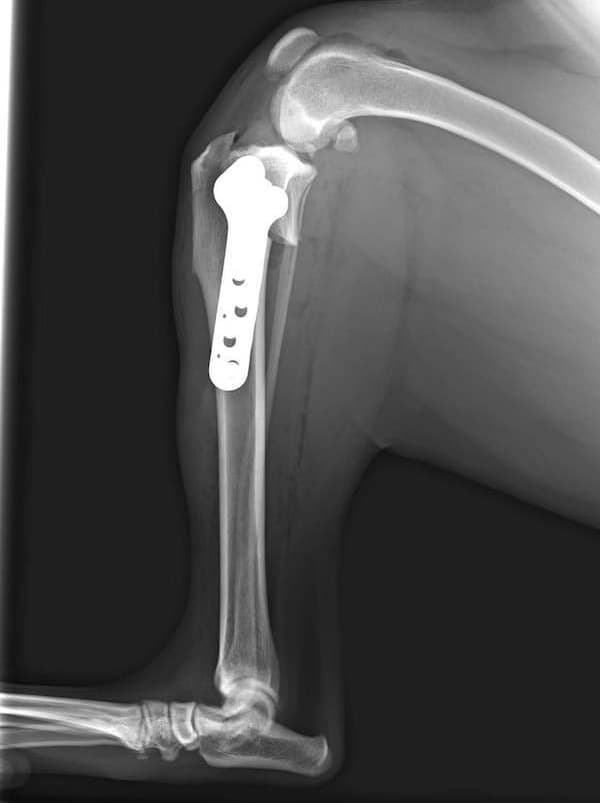

アメリカンコッカースパニエル 5歳

半年にわたる左後肢の跛行が認められるとのことで来院されました。触診にて左膝関節の疼痛、内側部の腫脹、膝蓋骨の内方脱臼を認めました。レントゲン検査にてfat pad signを伴う関節炎が認められたことから、前十字靭帯断裂と膝蓋骨内方脱臼( GradeⅢ)の併発と診断し、手術を行いました。術中の関節鏡検査にて前十字靭帯の完全断裂を確認、関節液検査にて感染を除外した後、TPLOと、滑車溝形成を始めとした膝蓋骨脱臼整復術を実施いたしました。

術後側面像

術後正面像

術前に25°であったTPAは、TPLO実施により7°に矯正されました。症例の歩行状態は良好です。